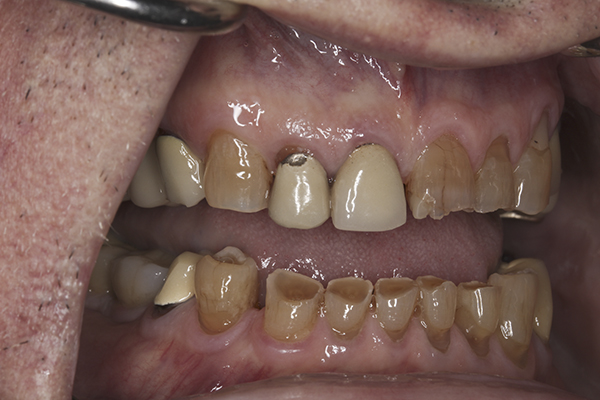

(9.) Preoperative right lateral, closed view.

Figure 9

(10.) Preoperative anterior, closed view. Note the end-to-end occlusion of the anterior teeth and the wear on the incisors and centrals resulting in no anterior or canine guidance.

Figure 10

(11.) Preoperative left lateral, closed view.

Figure 11

(12.) Preoperative right anterior, close-up view.

Figure 12

(13.) Preoperative anterior, close-up view.

Figure 13

(14.) Preoperative left anterior, close-up view.

Figure 14